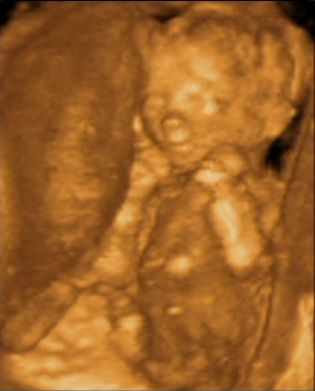

Ha lehet rakok fel képet az én KISFIAMRÓL!!! Voltunk 4D uh-on és ott láthattam őt. A képen 16 hetes!

Kép